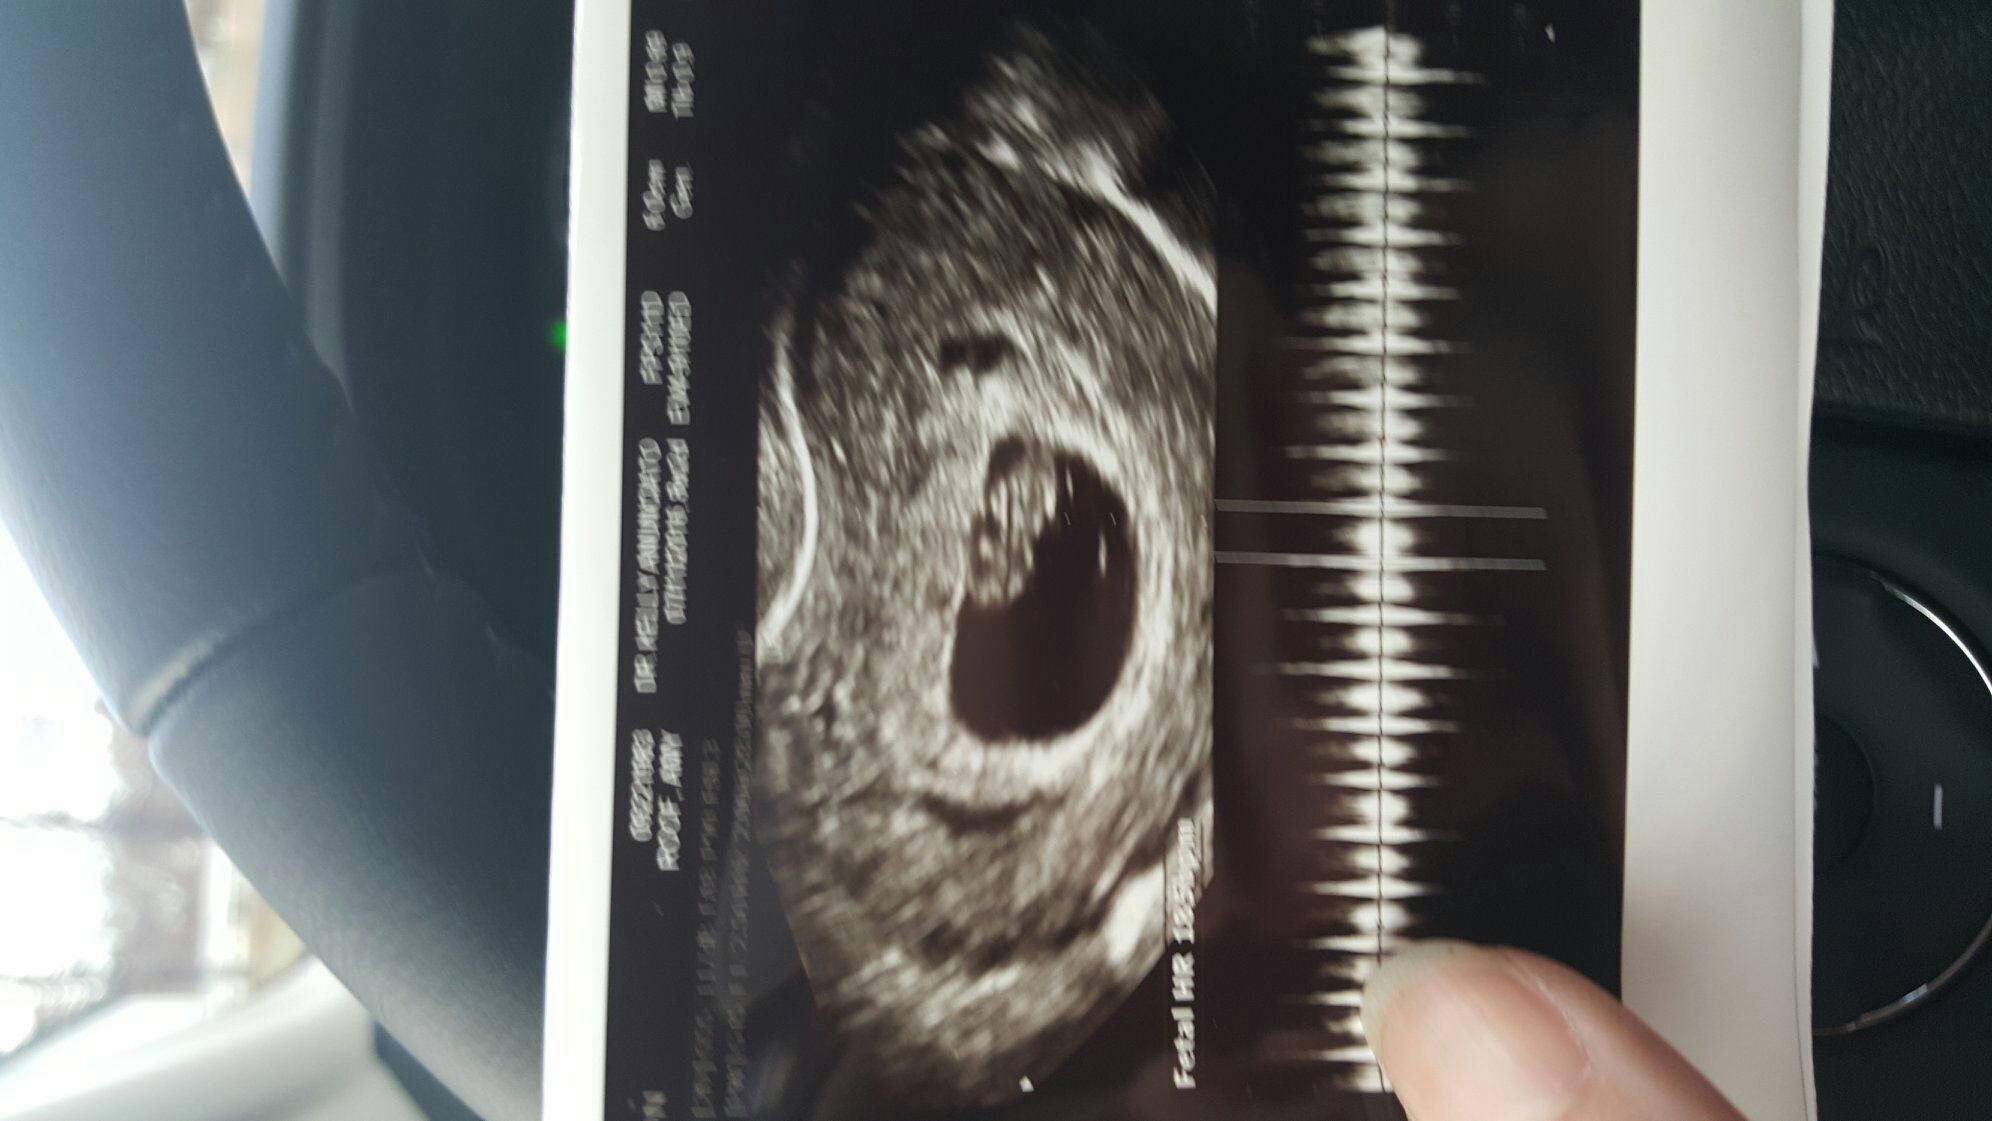

My name is Kristen and I'm 26 and single and scared and excited out of my mind. This is my first and a complete super baby because I was on the pill and told that I was completely infertile by my obgyn. So I'm tried to qualm my fear with the thought that I have an absolute miracle inside me. My doc and I both thought a was a lot further along but after my ultrasound yesterday turns out I'm only 5 weeks (couldn't even see a heart flutter which was a let down). I'm due July 31st and because I'm never on time for anything I think I'll end up being in the July mom club. Look forward to chatting with you all.

My doc and I both thought a was a lot further along but after my ultrasound yesterday turns out I'm only 5 weeks (couldn't even see a heart flutter which was a let down). I'm due July 31st and because I'm never on time for anything I think I'll end up being in the July mom club.

Hello! I'm Lindsay, and I'm due with a surprise #4 (even more of a surprise because I have a Mirena IUD). I have three other kids, ages 7, 5, and 3, and we live in San Antonio. I'm about 7+ weeks, due 7/21 (I'm guessing, not really sure when the last period was), and have a last minute ultrasound today to make sure everything is OK.